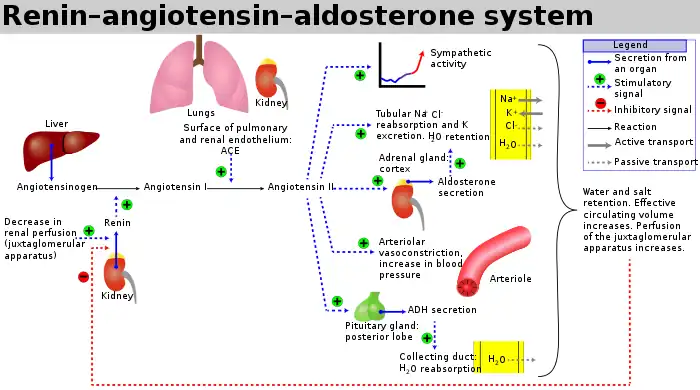

Hypertension induced by angiotensin II

The renin-angiotensin-aldosterone system (RAAS) regulates blood pressure, fluid and electrolyte homeostasis, and vascular resistance via release of hormones. The system is initiated by renin converting the precursor protein angiotensinogen into angiotensin I (Ang I). Ang I then gets converted to Ang II by the angiotensin-converting-enzyme (ACE) which then goes on to produce a number of different effects on the body. One such effect is inducing hypertension via Ang II and Ang metabolites produced by the degradation of Ang I and Ang II.[3] Ang II increases blood pressure by constricting blood vessels and it stimulates the production of aldosterone, which also increases blood pressure by increasing the volume of fluid in the body via increased sodium reabsorption by renal tubules in the kidney. Hypertension is associated with enhanced RAAS activity.

There are several Ang receptors in the body with the most common being AT1R, which is expressed in the heart, kidney, gut, blood vessels, and the brain. Ang II binds AT1R to produce vasoconstriction, inflammation, and endothelial dysfunction. Activation of AT2R has opposite effects of those to AT1R, exerting hypotensive effects.